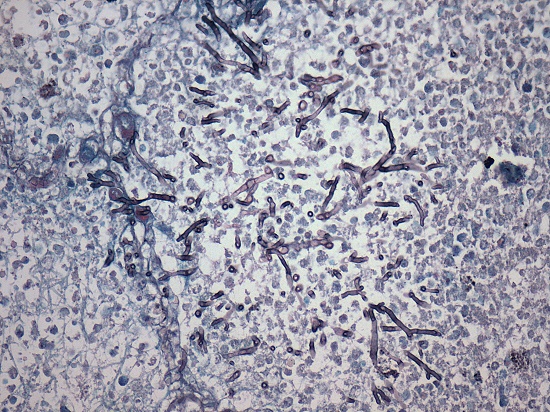

The abdomen showed a small amount of peritoneal effusion with fibrin deposits on the parietal peritoneal surface of the large bowel (Figure 5). On histological examination, the esophagus showed full thickness necrosis, and diffuse inflammatory infiltrate rich in neutrophils (necrotizing esophagitis) (Figure 6). Bacterial colonies, pseudohyphae, and yeasts consistent with Candida spp were detected on special stains in the esophagus, with invasion extended to the adventitia (Figure 7). Cultures or molecular tests for specific Candida species were not available for autopsy samples.